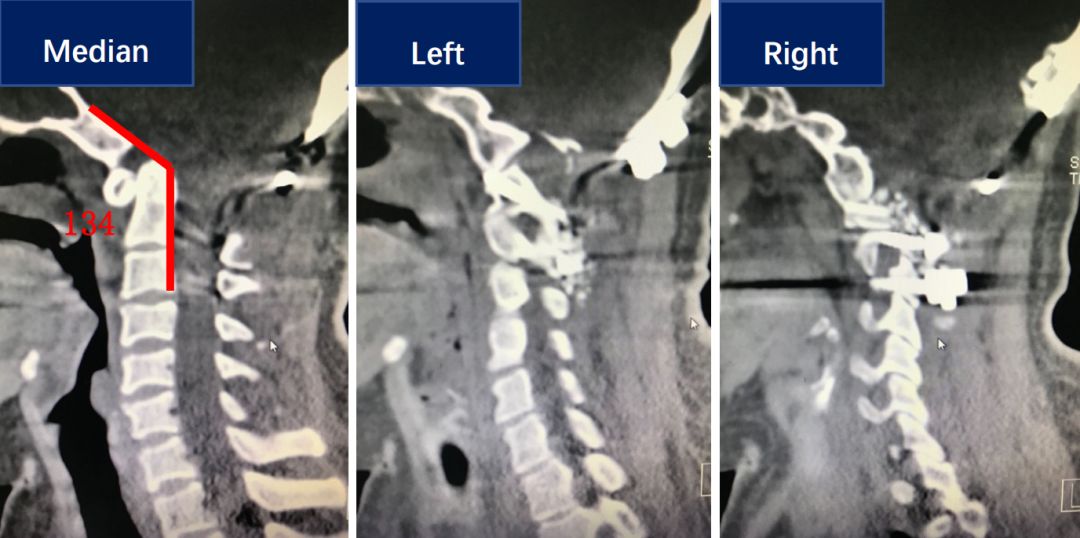

术前CT显示病人有明显的齿状突内陷,同时有双侧侧方关节的发育畸形。

术后患者颅底凹陷得到改善,同时斜坡颈椎角也有明显恢复,右侧绞索的侧方关节得到复位。

对比术前和术后的矢状位CT,可见齿状突内陷明显改善。